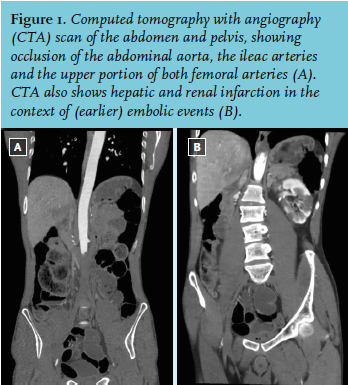

On physical examination, an Afro-American male was seen. He had a pulse of 123 beats/min, his blood pressure was 154/108 mmHg. His temperature was 35.7° Celsius, and his SpO2 was 97%. He had a complete paralysis of both his legs, and loss of sensibility. Both his legs were pale and cold. The pulsations of the femoral, popliteal, anterior tibial and dorsalis pedis arteries were absent on both sides. The neurological examination was normal: motoric and sensory function of the cranial nerves was intact, there was no paralysis or loss of sensibility of his upper extremities and the coordination was not impaired. The electrocardiogram (ECG) showed a sinus tachycardia of 130 beats/min, but no other abnormalities. Laboratory tests revealed a slightly elevated leukocyte count of 17.1 (normal value: 4.0-10.0 x 109/l), a C-reactive protein of 94 (CRP: 0-8 mg/l), an elevated lactate dehydrogenase level of 3068 (LDH: 0-248 U/l), a creatinine kinase level of 128,932 (CK: 0-145 U/l), an aspartate transaminase of 2155 (ASAT: 0-31 U/l), and an alanine transaminase of 365 (ALAT: 0-34 U/l). The arterial blood sample was normal with the exception of an elevated lactate of 2.9 (0.5-1.7 mmol/l). His vitamin B1, B6, B12 and his folic acid levels were within the normal range. Lumbar puncture showed a leukocyte count of 1.0 (0.0-5.0 x 106/l), a glucose of 4.2, and an albumin of 115.9 (100-300 mg/l); there were no erythrocytes. Magnetic resonance imaging of the cerebrum, and thoracic and lumbar spine showed no abnormalities. A computed tomography with angiography scan was performed (figure 1).

WHAT IS YOUR DIAGNOSIS?